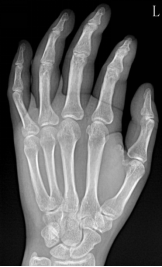

类风湿性关节炎

多发性、非特异性慢性滑膜炎症为主要表现的全身性疾病

多见于20-40女性

受累关节多呈对称性,以手足小关节为主

影像表现:①关节软组织肿胀;②关节间隙变窄、关节面边缘骨侵蚀;③软骨下多发囊样透亮区;④骨质疏松;⑤ 关节畸形和关节强直

F,55Y